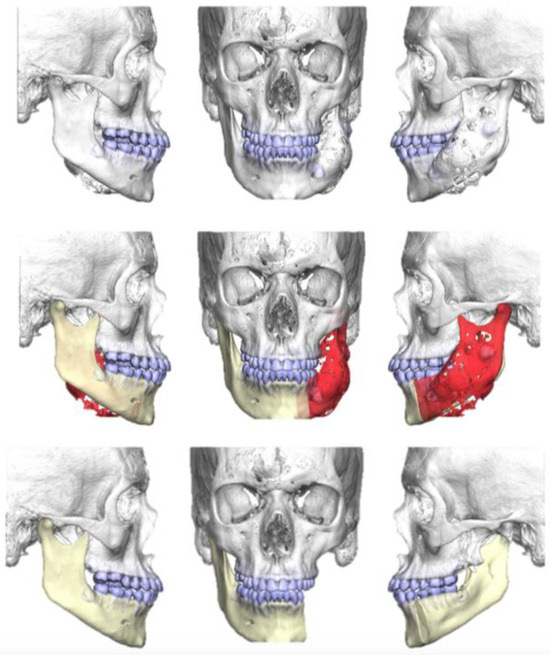

2.2. Case 2